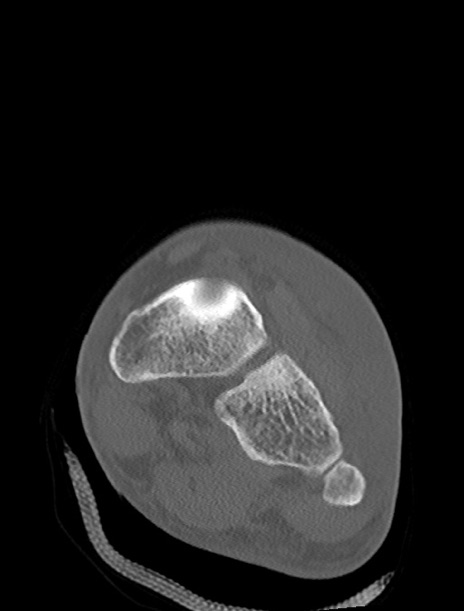

左足関節CT

横断像